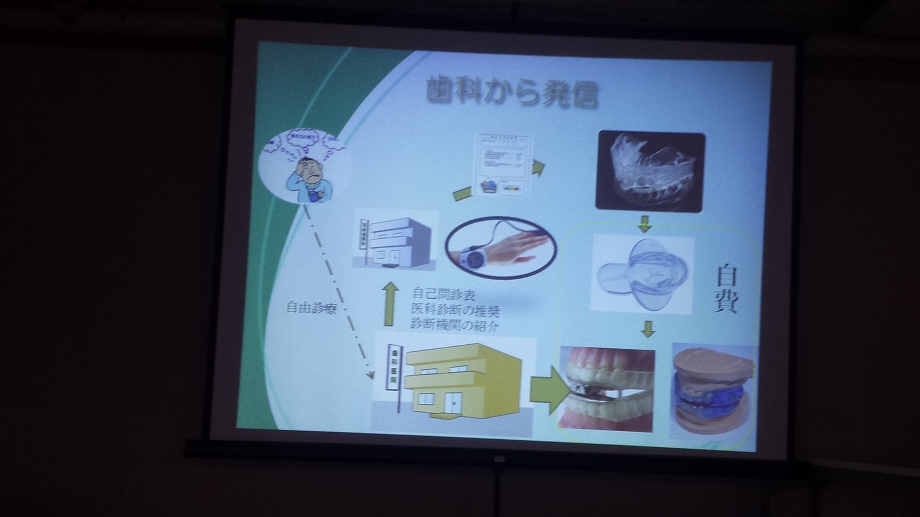

![]() 虫歯や入れ歯などの一般の歯科治療

虫歯や入れ歯などの一般の歯科治療

![]() 歯石取りや歯のクリーニングや歯周病のメンテナンス

歯石取りや歯のクリーニングや歯周病のメンテナンス

![]() 親知らずの抜歯などの口腔外科

親知らずの抜歯などの口腔外科

![]() 歯並びを美しく戻す歯科矯正

歯並びを美しく戻す歯科矯正

![]() 白い歯の詰め物やかぶせ物を入れる審美歯科

白い歯の詰め物やかぶせ物を入れる審美歯科

![]() 歯を白く漂白するホワイトニング

歯を白く漂白するホワイトニング

![]() 金属のバネを使わないノンクラスプデンチャーなどの入れ歯

金属のバネを使わないノンクラスプデンチャーなどの入れ歯

![]() 歯ぎしり防止やスポーツ用のマウスピース

歯ぎしり防止やスポーツ用のマウスピース

![]() インプラントなどの先端医療の紹介

インプラントなどの先端医療の紹介

などなど![]() お口に関してのいろんな悩み事や、相談ごと、疑問などをお気軽にお話しください

お口に関してのいろんな悩み事や、相談ごと、疑問などをお気軽にお話しください![]()